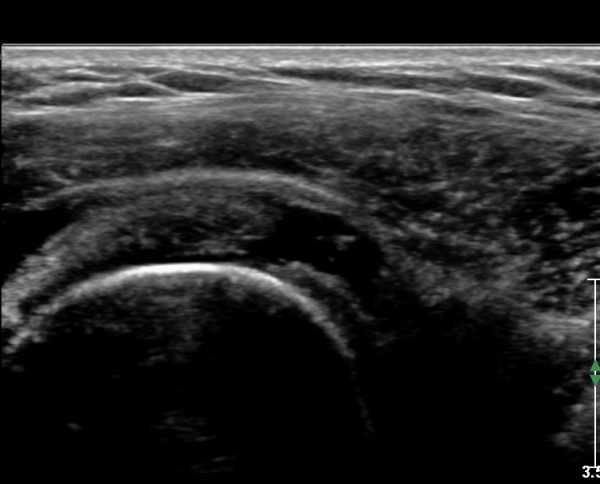

ŽÃËÀÚ¸¦ Á»´õ ¸»´ÜÀ¸·Î À̵¿ ÈÄ(¶Ç´Â ¾Æ·¡·Î ±â¿ïÀÎ ÈÄ) ³»ÃøºÎ¸¦ Á¶ÀýÇÏ´Ï °ß°©ÇÏ±Ù°Ç Ç¥ÃþÀ¸·Î Á¡¾×³¶³» ¼ö¾×Àú·ù°¡ °üÂûµÈ´Ù(»çÁö 3, 4). ŽÃËÀÚ¸¦ Á¶Á¤ÇÏ´Ï ÀÌµÎ¹Ú°Ç ÁÖÀ§ ¼ö¾× Àú·ù¿Í Á¡¾×³¶³» ¼ö¾×Àú·ù°¡ °üÂûµÇ¾î Á¡¾×³¶¿°°ú Ȱ¾×¸·¿°ÀÌ ÀÖÀ½À» ¾Ë ¼ö ÀÖ´Ù(»çÁø 5).

±ØÇ졂 Á¾´Ü¸é °Ë»ç¿¡¼ Àá¾×³¶³» ¼ö¾×Àú·ù°¡ °üÂûµÇ°í(»çÁø 9) ÅÒÃËÀÚ¸¦ Á¶±Ý ³»ÃøÀ¸·Î À̵¿ÇÏ´Ï ±Ø»ó°ÇÀÌ ¼Ò½ÇµÇ°í ¼ö¾×Àú·ù°¡ °üÂûµÈ´Ù(»çÁø 10).